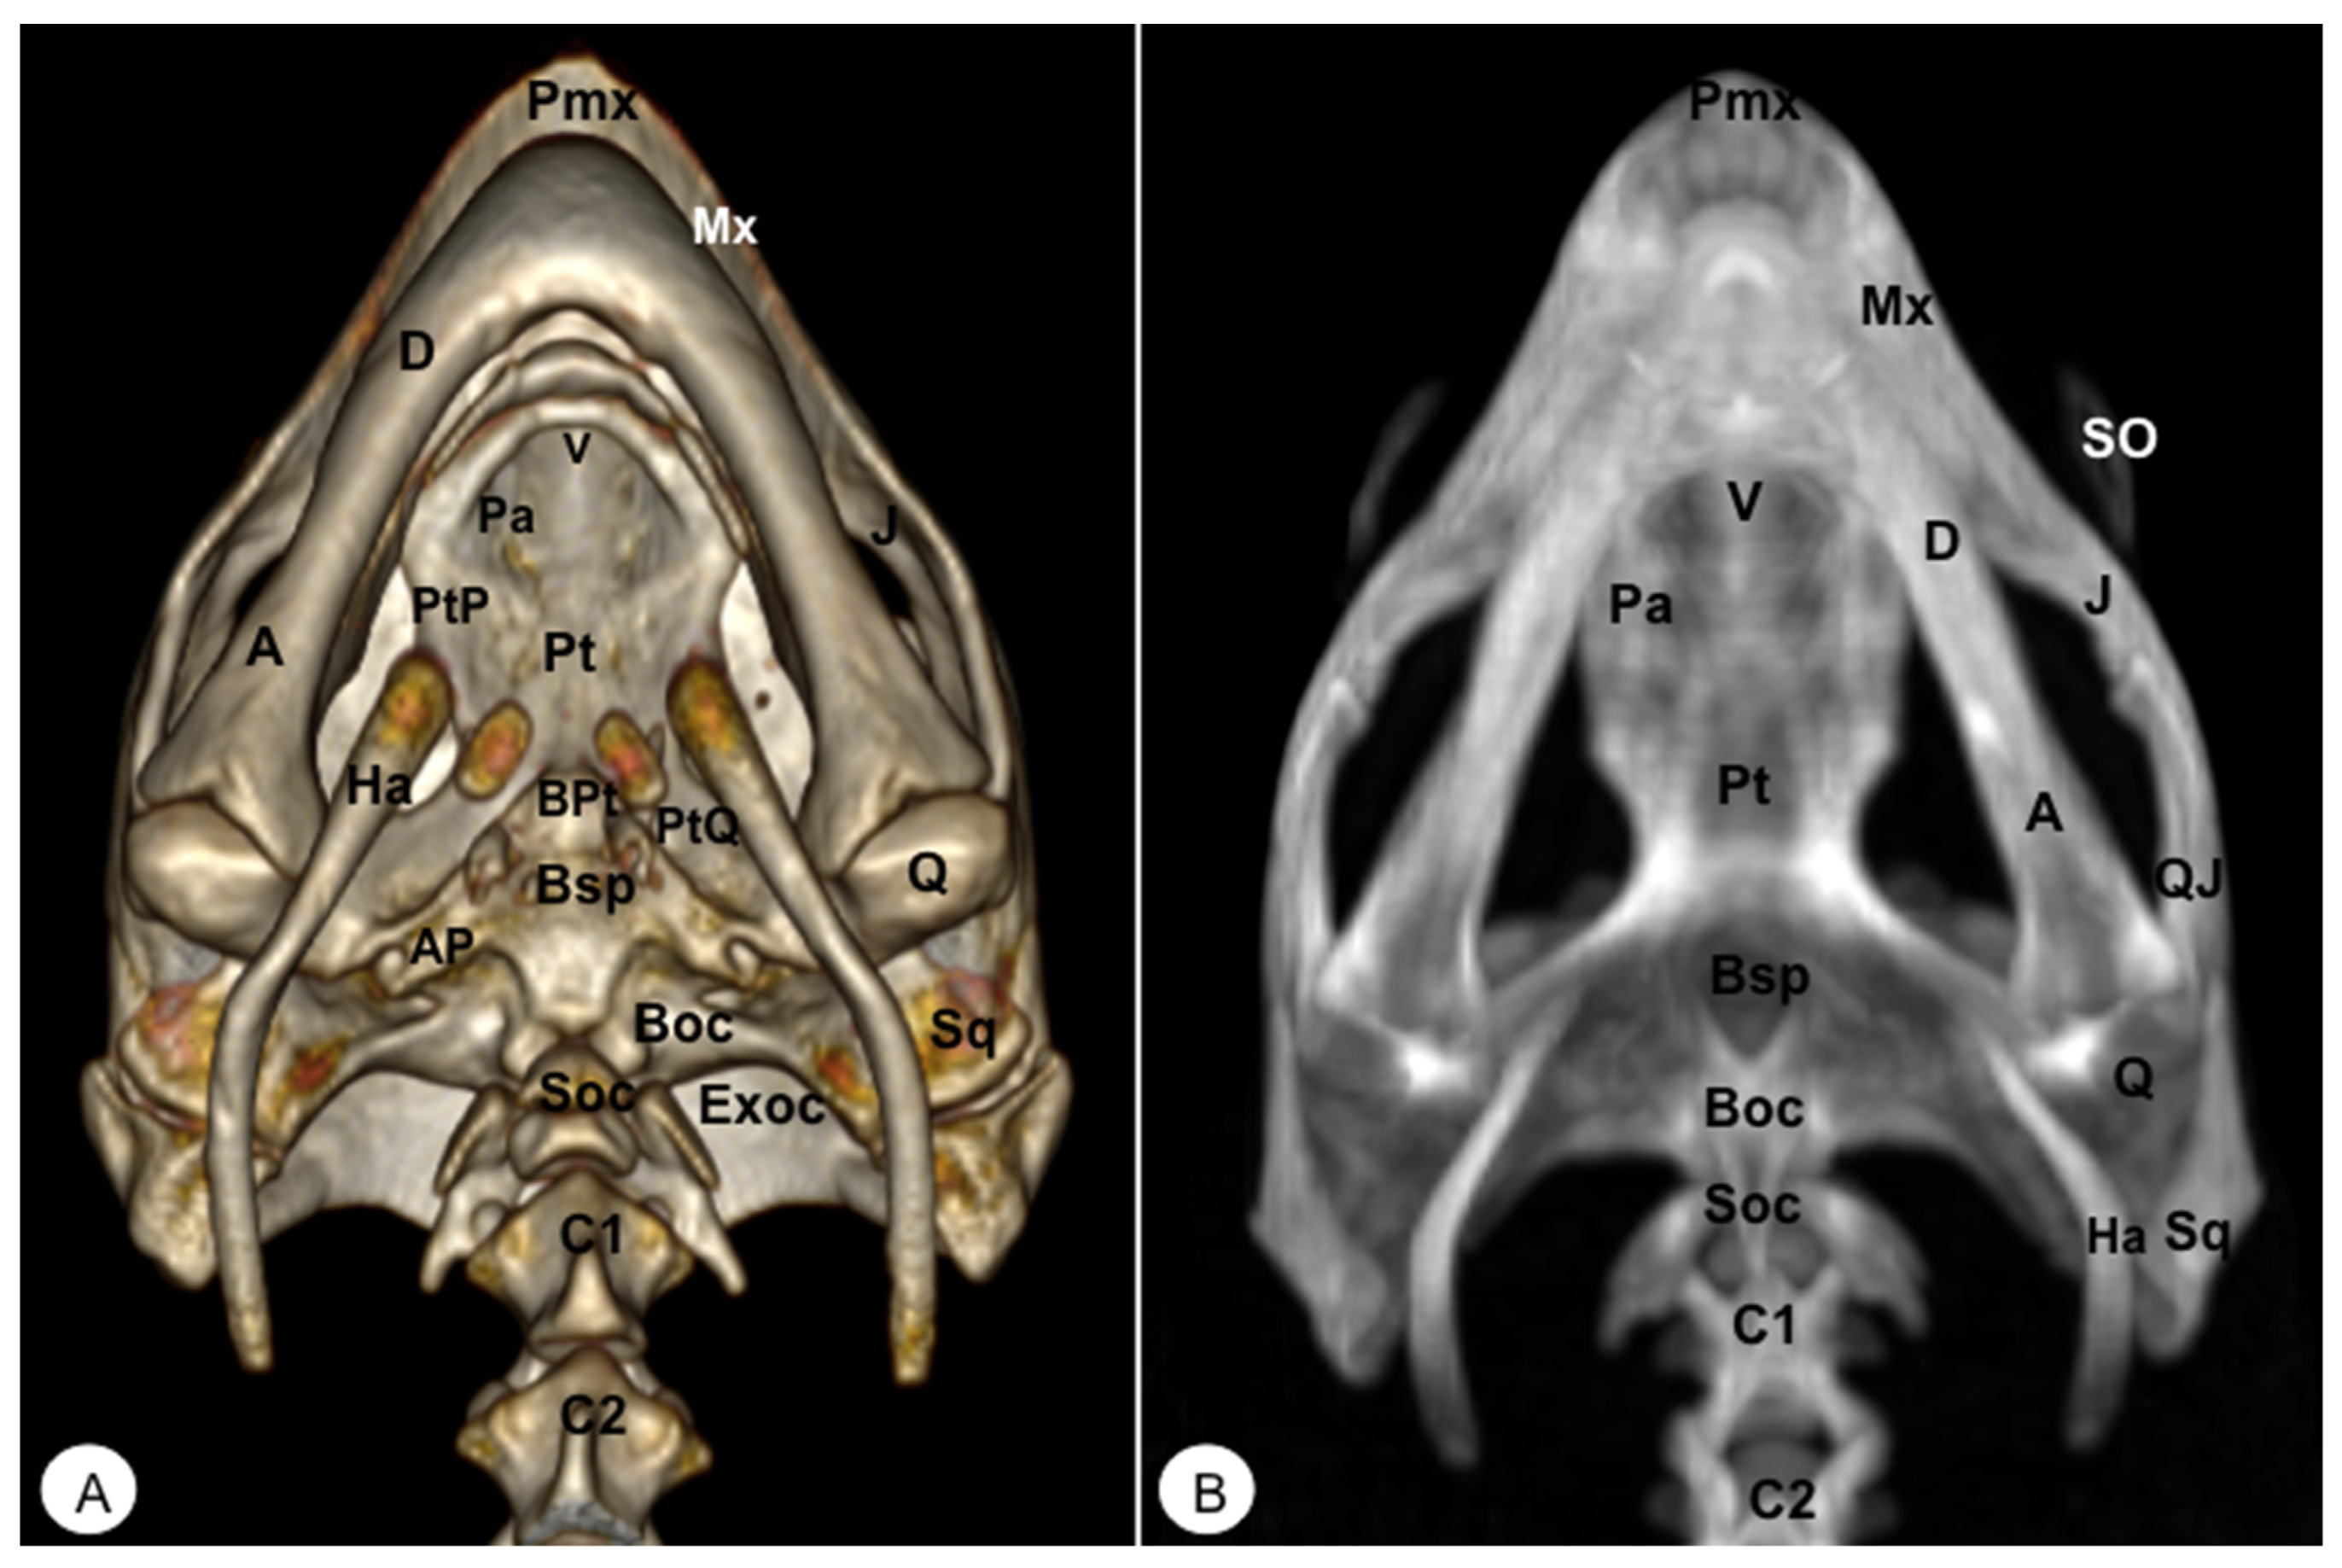

Different rostral, lateral, ventral, dorsal, and caudal VR and MIP images were obtained for better visualization and description of the different bones comprising the head (dermatocranium, neurocranium, and mandibula) of the turtle and the iguana (Figure 2, Figure 3, Figure 4, Figure 5, Figure 6, Figure 7, Figure 8, Figure 9, Figure 10 and Figure 11). We selected images that better matched each other, providing valuable information.

Figure 9. Head of Iguana iguana. (A) Ventral VR image. (B) Ventral MIP image. (C) Ventral VR image without Hyoid apparatus. D: Dentary bone. An: Angular bone. Art: Articular bone. V Vomer. Pa: Palatine bone. Pt: Pterygoid bone. Ec: Ectopterygoid. PtP: Pterygoid palatine process. PtQ: Pterygoid quadrate process. BPt: Basipterygoid process. PBsp: Parabasisphenoid bone. Cp: Cultriform process. OC: Occipital condyle. Ha: Hyoid apparatus. AP: Alar process.

Animals 13 00621 g009

Figure 10. Head of Iguana iguana. (A) Dorsal VR view. (B) Dorsal MIP view. Pmx: Premaxillary bone. Mx: Maxilla. N: Nasal. PrF: Prefrontal. F: Frontal. PsF: Postfrontal. Po: Postorbital. J: Jugal. Pt: Pterygoid. Ec: Ectopterygoid. Q: Quadrate. Sq: Squamousal. St: Supratemporal. P: Parietal. Soc: Supraoccipital. Art: Articular. Ha: Hyoid apparatus.

Animals 13 00621 g010